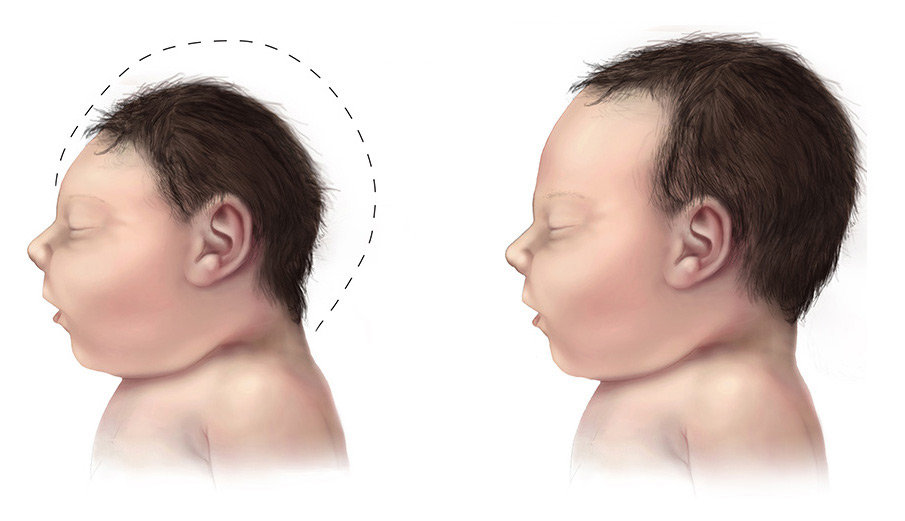

Nu visar tre oberoende forskargrupper resultat på att zikaviruset kan ta sig in i moderkakan och sedan angripa fostrets hjärna.